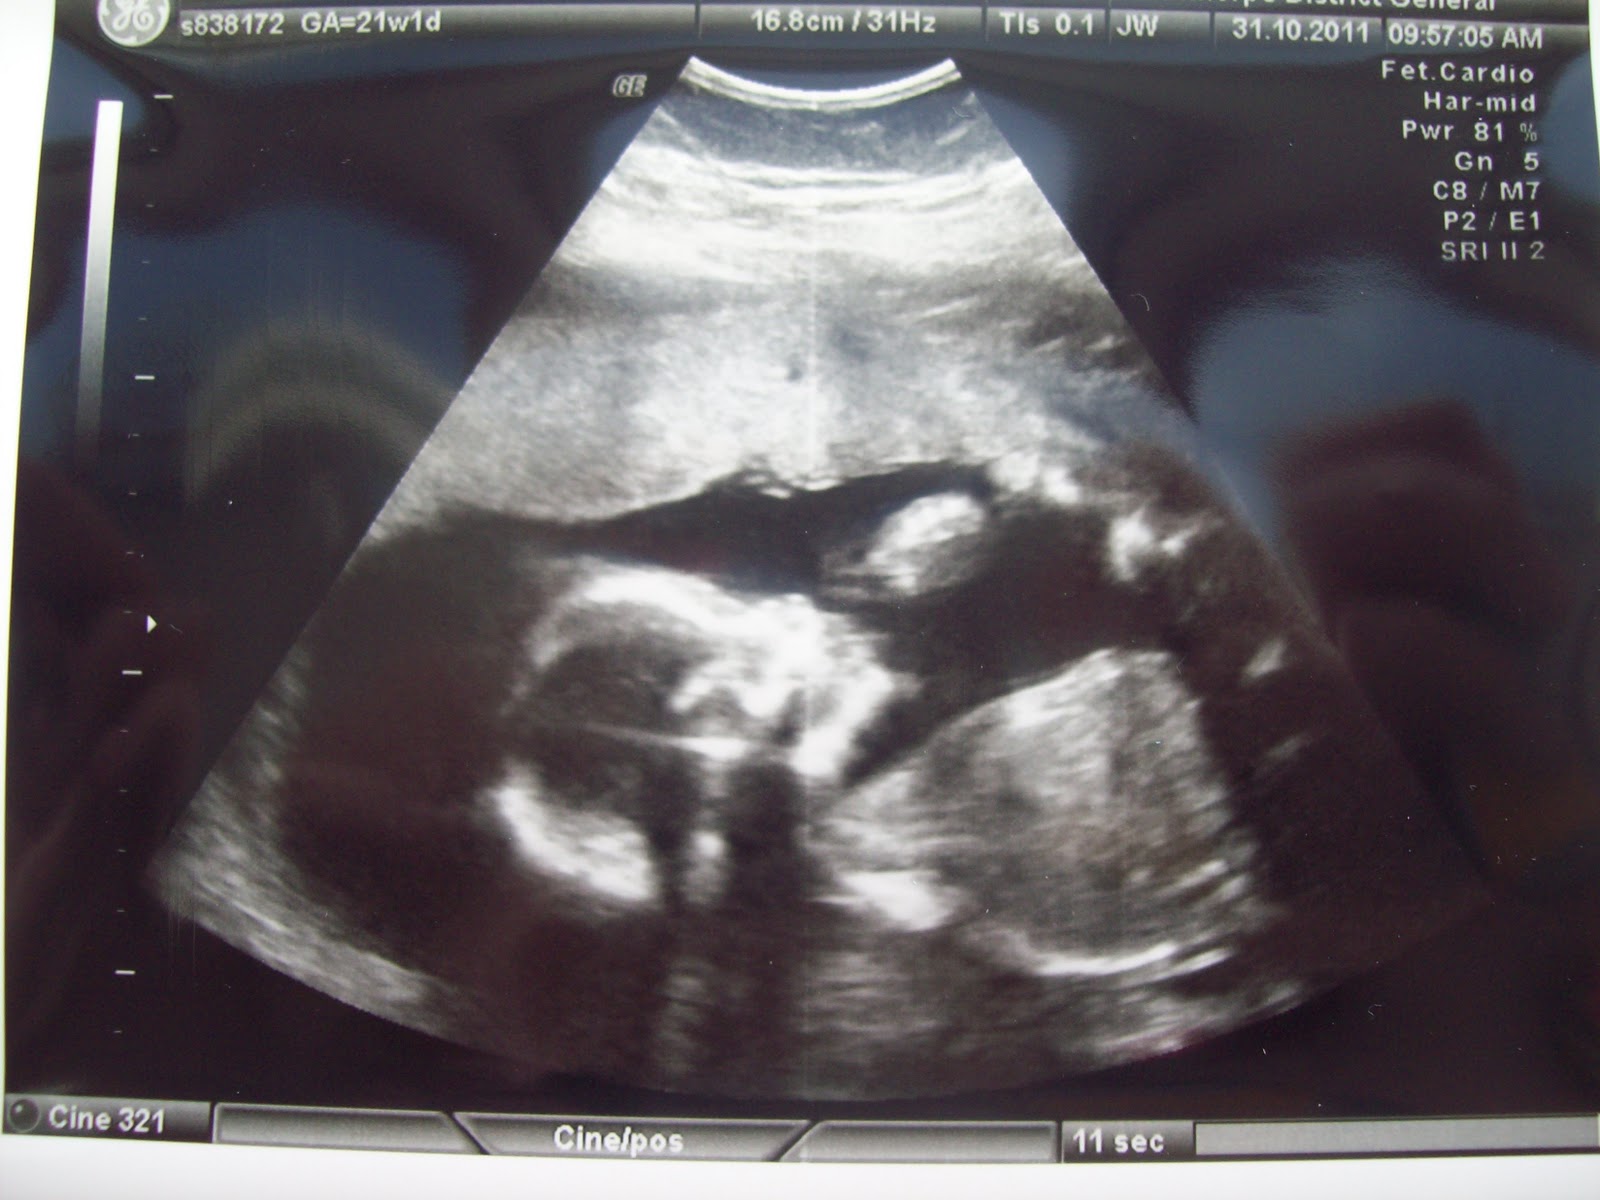

Yesterday we had our 20 week anomaly scan. I’m sure you all know by now that we wanted to find out the gender, and luckily baby had their legs uncrossed and let us see! Baby G is a…. BOY! Mummy’s instinct was right! (As was the old wives tales gender predictor, the astrological balance predictor, gender swaying BD timing, and the Baby Centre gender predictor) We are absolutely over the moon, I can’t stop smiling! Now, since I can remember, I always imagined myself having a baby girl, until I was actually pregnant, from about 6 or 7 weeks I knew he was a boy, just had that feeling…

Of course this scan was a detailed scan to check baby over too, and I’m delighted to say that he is growing well! Was amazing seeing him on the screen again, and when the sonographer told us he was a boy, I must admit I had a tear in my eye! Though at first baby had his hands over his eyes, he obviously didn’t want us to see him!